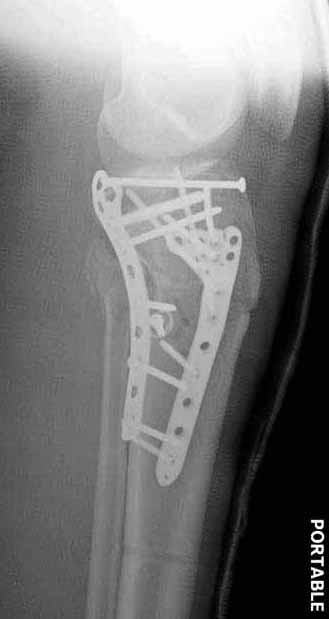

Двухколоннный перелом тибиал плато с вовлечением проксимального диафиза. Внутрисуставной компонент без смещения, и такой перелом можно лечить любым из описанных методов, о которых говорят наши коллеги.

Удобно аппаратом Илизарова или интрамедуллярным гвоздем. Гвозди не так сложно, как пугают, тем более Александр готов помощь с методичкой. Сперва надо установить компрессирующие шурупы на мыщелки. Давно отказались в пользу 3.5-4.0 мм кортикальных вместо толстых спонгиозных, потому что не доказаны преимущества толстых шурупов. Тонкие шурупы в субхондральной зоне смотрятся намного элегантнее, чем толстые 6.5.

Это мероприятие превращает перелом в простой диафизарный, который легко можно фиксировать гвоздем. Шурупы надо установить сзади предполагаемого места введения гвоздя.

Частая ошибка, когда фиксацию двух колонного перелома проводят одиночной пластиной, т.е с одной стороны, и такая фиксация не удерживает, происходит вторичноое смещение. Необходимо нейтрализовать второй пластиной или дополнительным наружным фиксатором.

Если у вас, кроме пластины, нет другого альтернативного варианта, тогда, учитывая мягкотканые проблемы с наружной стороны, я бы рекомендовал операцию делать в два этапа. Преимущества, сперва репозиция и фиксация перелома с медиальной стороны, а затем, после улучшения состояния мягких тканей, зафиксировать с латеральной стороны. Современные пластины имеют латеральный Jig для перкутанных мини доступов.

В приложении этапы фиксации Both Column Fx и пластиной Synthes для плеча при переломе медиального мыщелка.